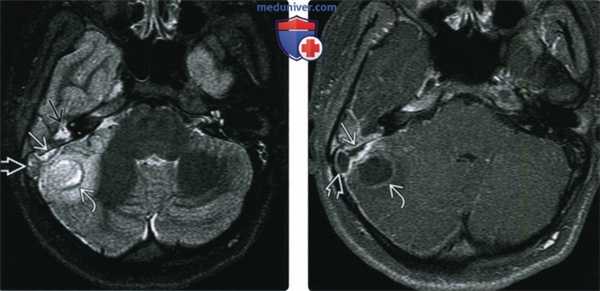

(Слева) При аксиальной МРТ Т2 ВИ FS у девочки 15 лет с болезненностью с области сосцевидного отростка и головной болью визуализируется гиперинтенсивный эпидуральный абсцесс возле кортикального слоя сосцевидного отростка, гипоинтенсивный тромб в сигмовидном синусе и абсцесс мозжечка, окруженный гипоинтенсивным «ободком» и зоной отека. В прилежащих ячейках сосцевидною отростка определяется жидкость.

(Справа) При аксиальной MPT Т1 ВИ С+ у этого же пациента визуализируется эпидуральный абсцесс, тромб в сигмовидном синусе и абсцесс мозжечка - гипоинтенсивные с периферическим накоплением контраста.